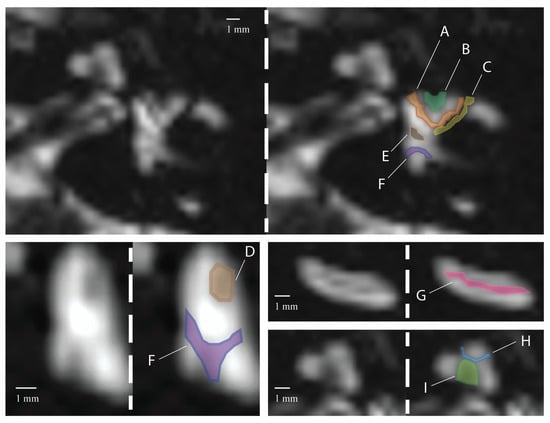

3.1. Signal Areas in the Inner Ear

| A | B | C | D | E | F | G | H | I | ||

| Right ear | Reader 1 | 8 | 6 | 6 | 7 | 9 | 9 | 8 | 10 | 10 |

| Reader 2 | 8 | 6 | 5 | 7 | 9 | 9 | 8 | 9 | 10 | |

| Left ear | Reader 1 | 10 | 7 | 4 | 7 | 10 | 10 | 8 | 10 | 10 |

| Reader 2 | 10 | 7 | 4 | 7 | 10 | 10 | 8 | 10 | 10 | |

| Right ear | 27 (90.0%) | 21 (70.0%) | 10 (30.3%) | 22 (73.3%) | 28 (93.3%) | 29 (96.7%) | 24 (80.0%) | 29 (96.7%) | 30 (100%) |

| Left ear | 28 (93.3%) | 21 (70.0%) | 14 (46.7%) | 25 (83.3%) | 26 (86.7%) | 29 (96.7%) | 26 (86.7%) | 30 (100%) | 30 (100%) |